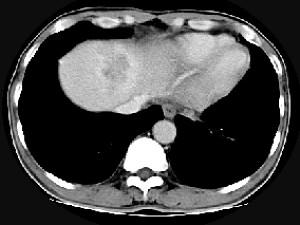

问题 男,61岁,寒战高热,右上腹痛,白细胞计数升高,CT检查如图,最可能的诊断是 ( )

选项 A、炎性肉芽肿 B、肝转移瘤 C、肝血管瘤 D、肝脓肿 E、原发性肝癌

答案 D